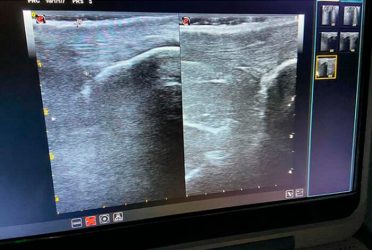

- Seminario internacional en ecografía diagnóstica en patología de pie y tobillo